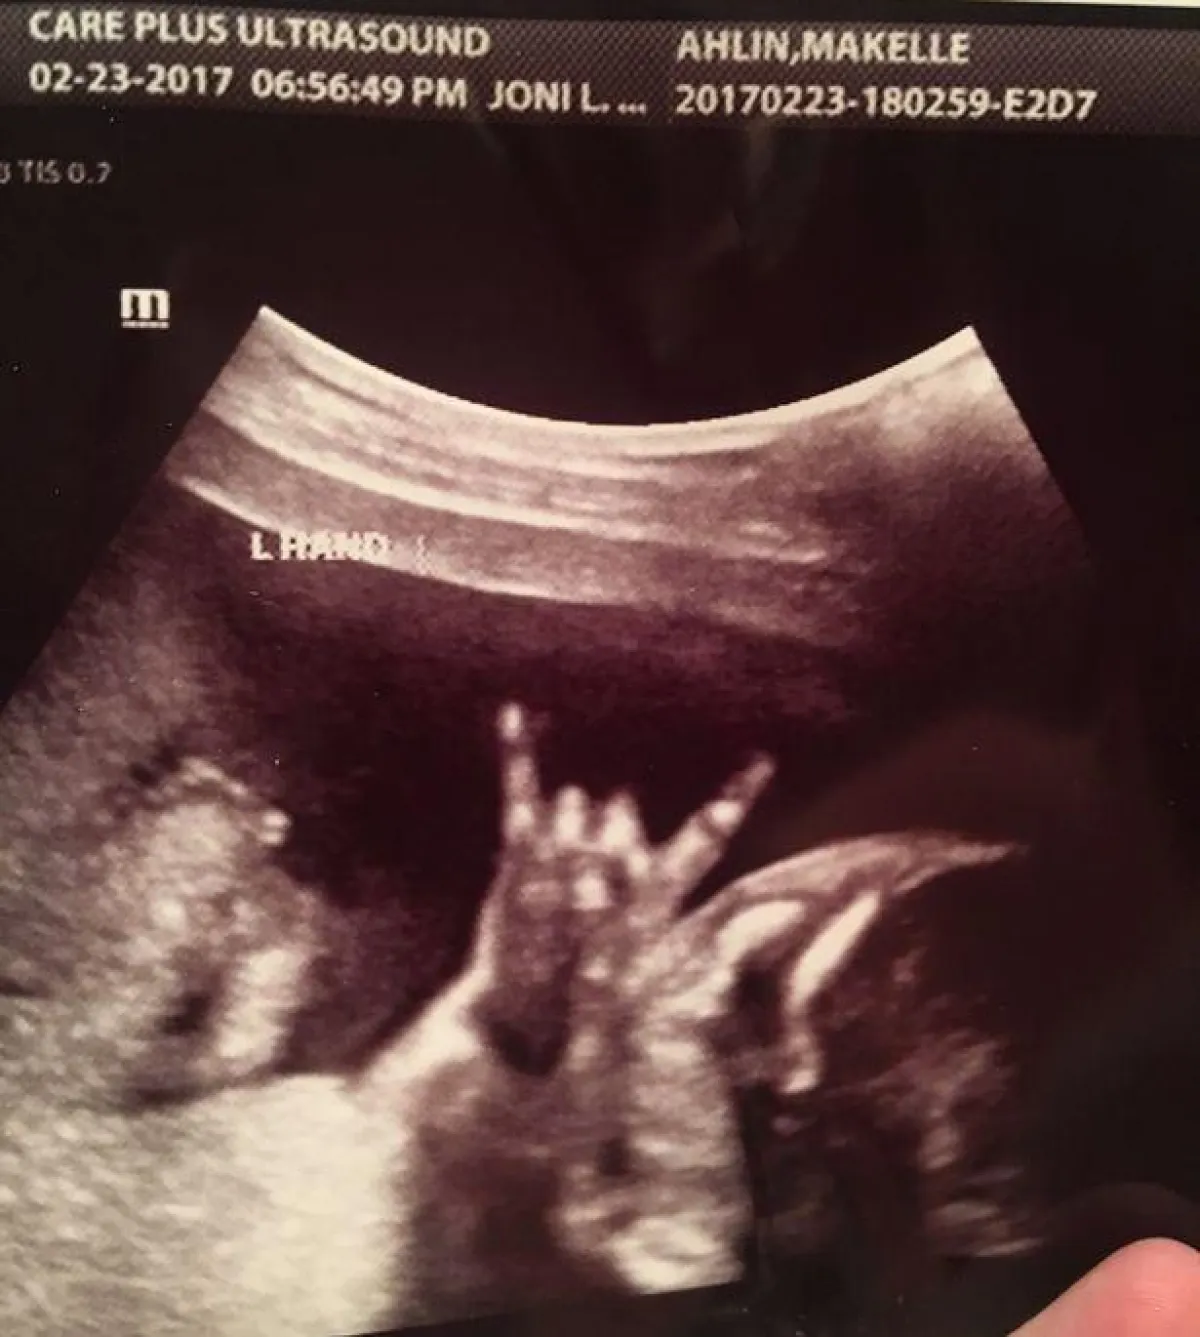

في لقطة مثيرة لجنين داخل رحم أمه، فوجئ الأبوين والطبيب أثناء إجراء أشعة بالموجات فوق الصوتية بالجنين يشير إليهم مما تسبب في اندهاشهم جميعا .

ونشرت صحيفة "ميرور" البريطانية صورة الأشعة فوق الصوتية للجنين داخل رحم أمه، وهي في شهرها السادس، وهو يشير لوالديه بعلامة الشيطان والتي تعد شعاراً للماسونية وتبعث الشر في النفس، ولكن الوالدان تقبلا الأمر بشكل مرح، واعتبرا أن الجنين حاول بتلك الإشارة جذب انتباههما .

وقام الأب جاريد وزوجته ماكلين بنشر صورة الجنين على موقع التواصل الإجتماعي فيس بوك، فحققت انتشاراً كبيراً خلال ساعات، تحت عنوان "جنين يرفع قرون الشيطان".

وقال الأب: "أطفالنا دائماً يعطوننا الإشارات حتى قبل مجيئهم للحياة.. إنه شيء رائع ونحن سعداء بذلك". فيما قال الطبيب إن الجنين دائماً ما يمنح والديه إشارة خلال إجراء الأشعة، ولكن هذا الطفل جاء بإشارة مختلفة فعلى ما يبدو أنه يحب الموسيقى والضوضاء.